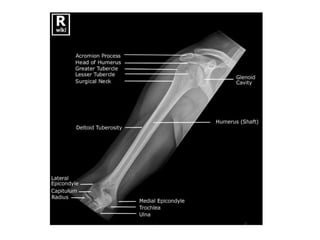

Anatomy

• extends from the surgical neck proximally to

the humeral condyles distally.

• Cylindrical shape proximally

• conical in its middle 1/3

• Flattened dramatically in the coronal plane

distally .

• muscles are divided into anterior flexor and

posterior extensor compartments .